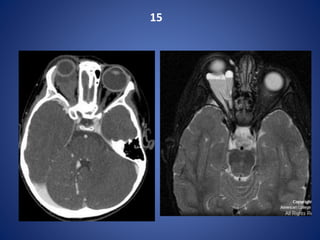

Dehiscent jugular bulb

15

INTRAORBITAL LYMPHATIC MALFORMATION

There is an intraconal multilobulated mass with a fluid-fluid level and mild right globe

proptosis.

Vascular lesions account for 5-20% of all orbital masses, and the two most common orbital

vascular lesions are venous malformations (formerly known as cavernous hemangiomas) and

lymphatic malformations (LM) ( formerly known as lymphangiomas).

Intraorbital venous-lymphatic malformations are present at birth, but tend not to be

discovered clinically until early childhood when they enlarge as a result of either

intralesional hemorrhage or lymphoid hyperplasia and result in acute proptosis.

Radiologic imaging of intraorbital LMs demonstrates unencapsulated, irregular,

lobulated, and multicompartmental masses.

These lesions can have cystic as well as more solid components. The cystic elements

of these masses commonly exhibit fluid-fluid levels as a result of intralesional

hemorrhage

Ultrasound images of LMs demonstrate heterogeneous, ill-defined lesions with

anechoic cystic portions and extraconal extension.

On CT, these masses exhibit ill-defined borders, irregular attenuations, and variable

enhancement with peripheral rim enhancement in cystic regions. Additionally,

calcified phleboliths can be seen on CT in venous portions of these lesions.

MR imaging -

LMs demonstrate iso- to slightly high signal intensities on T1-weighted images and

very high signal intensities on T2-weighted images.